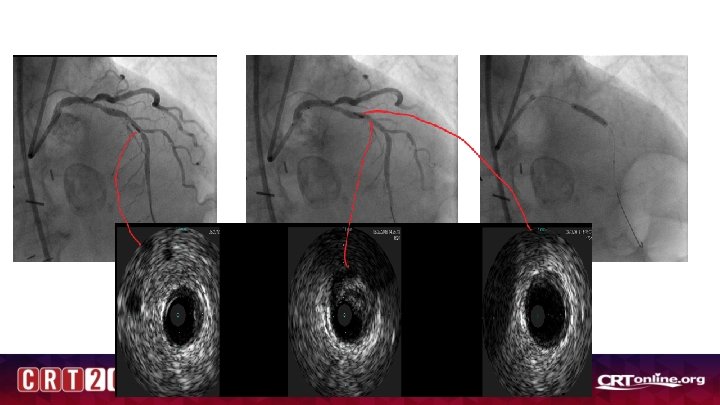

Unclear Culprit

Conclusions • Event rate is higher in deferred lesions in NSTEMI /ACS patients • Non-culprit vessel FFR is reliable and did not change significantly at follow up (although only at ~1 month- 6 month may be different) • Culprit vessel –FFR reliable and better than Angio-guided, but may be falsely negative in patients with high troponins and CRP and higher LVEDP (20 -25% of patients) -Also trend towards more events , spontaneous MI at follow up • IFR vs FFR data is ACS is interesting and needs further study • Co-Registration with resting indices may have promise in unclear culprit subsets